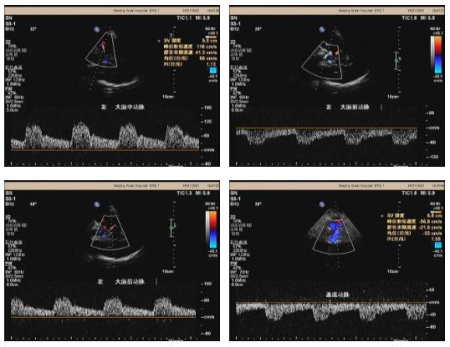

用于高危人群腦卒中篩查的頸腦動(dòng)脈一體化超聲檢查包括經(jīng)顱多普勒超聲(TCCD)和頸動(dòng)脈彩超。經(jīng)顱多普勒超聲(TCCD)是近年來(lái)發(fā)展的一種無(wú)創(chuàng)可視化腦血管超聲檢查方法,能夠直觀地識(shí)別顱內(nèi)結(jié)構(gòu),精準(zhǔn)定位顱內(nèi)血管,通過(guò)角度調(diào)整,能準(zhǔn)確檢測(cè)顱內(nèi)Willis環(huán)的血流動(dòng)力學(xué)變化,與DSA、CTA/MRA、TCD相比,TCCD可提供許多互補(bǔ)診斷信息。頸動(dòng)脈彩超可以測(cè)量血管內(nèi)-中膜厚度、斑塊大小、評(píng)估斑塊的穩(wěn)定性及判斷頸動(dòng)脈的狹窄程度。單獨(dú)的顱內(nèi)血管檢查或者單獨(dú)的頸部血管檢查無(wú)法對(duì)腦、頸動(dòng)脈血流動(dòng)力學(xué)的改變進(jìn)行整體化評(píng)估,會(huì)遺漏很多重要的血流動(dòng)力學(xué)改變信息。因此頸腦動(dòng)脈一體化血管超聲技術(shù),對(duì)頸腦部血管情況的觀察更加全面,綜合整體因素,可以提高診斷準(zhǔn)確率,減少漏診與誤診,為臨床治療提供更為精確的診斷報(bào)告。

目前,我院物理診斷科彩超室已全面開(kāi)展頸腦一體化血管超聲檢查技術(shù),服務(wù)廣大患者,為腦血管疾病的早期篩查及診斷提供了重要的技術(shù)支持。此前彩超室已成功舉辦過(guò)《頸腦一體化超聲在腦血管疾病中的診療規(guī)范新進(jìn)展》線上繼續(xù)教育學(xué)習(xí)班,吸引近萬(wàn)人次的觀看,推廣規(guī)范化頸腦一體化超聲檢查技術(shù),提高診療水平。物理診斷科彩超室全體人員在劉犇主任帶領(lǐng)下刻苦鉆研、團(tuán)結(jié)協(xié)作,積極開(kāi)展各項(xiàng)新技術(shù)、新應(yīng)用,滿足臨床需求,致力于高精尖的診療技術(shù)研究,為患者的診斷及治療提供可靠有效數(shù)據(jù)。